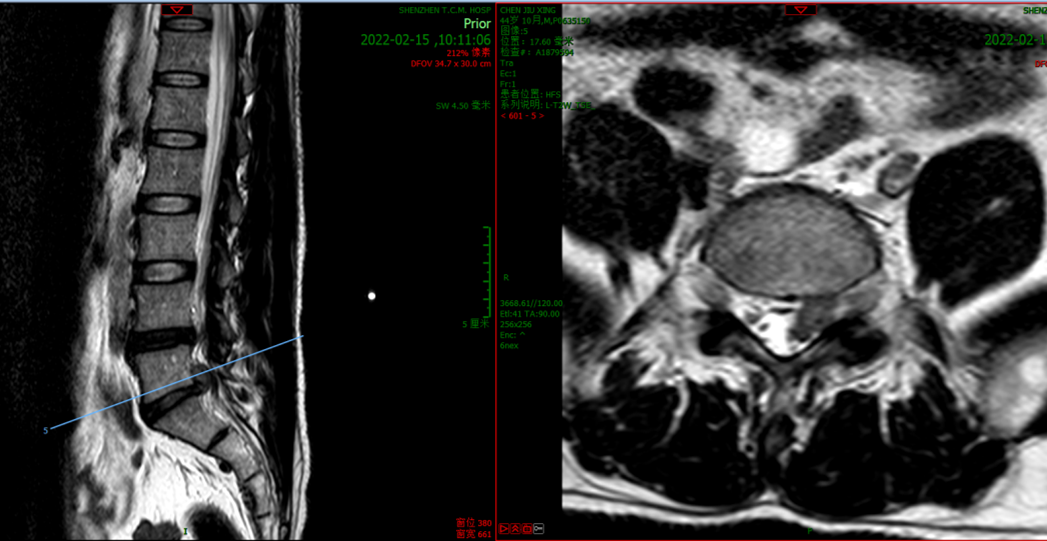

术前检查(图片)

经过仔细询问病史、查体及结合影像学检查后,患者诊断为腰椎管狭窄症(L4/5、L5/S1),合并L5/S1椎间盘巨大突出。经科室团队反复讨论研究手术方案,最终决定在天玑骨科机器人辅助下完成这例腰椎手术。